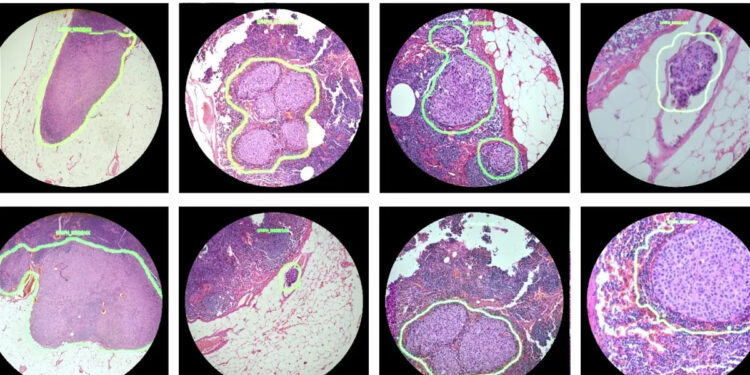

El “microscopio de realidad aumentada” (ARM) tiene como objetivo no solo aumentar el tamaño de las muestras analizadas para su revisión por parte de científicos, sino también superponer indicadores visuales generados por una inteligencia artificial entrenada. Estos indicadores pueden incluir mapas de calor o contornos de objetos en tiempo real, lo que simplificaría la clasificación de muestras y permitiría una identificación más precisa de nódulos, células anómalas e incluso patógenos no deseados en las muestras.

A pesar de que el ARM se mostró en 2018, nunca se utilizó para el diagnóstico de pacientes ni pasó de la fase de prototipo. Google ha fabricado hasta 13 prototipos del ARM y está trabajando en pruebas y desarrollos adicionales para su homologación. La ambiciosa meta es crear un sistema que se pueda adaptar a los microscopios de luz existentes en hospitales y clínicas.